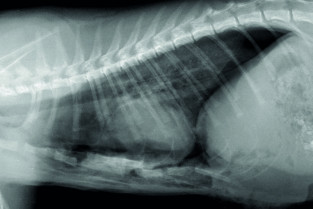

- décrire les principes à respecter pour obtenir une radiographie thoracique de bonne qualité ;

- adopter une méthodologie pour interpréter les affections de la cage thoracique, de la plèvre, du médiastin et des poumons chez les carnivores domestiques ;

- décrire l’aspect normal et anormal de la cage thoracique, de la plèvre, du médiastin et des poumons chez les carnivores domestiques.